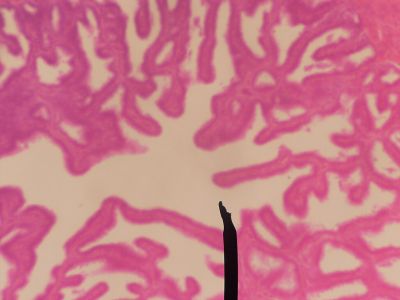

This is a histology slide of the seminal vesicle.